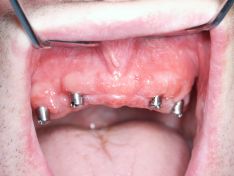

impianti inseriti e' possibile notare i difetti infraoosi

impianti inseriti

i quattro impianti con i rispettivi monconi e la sutura